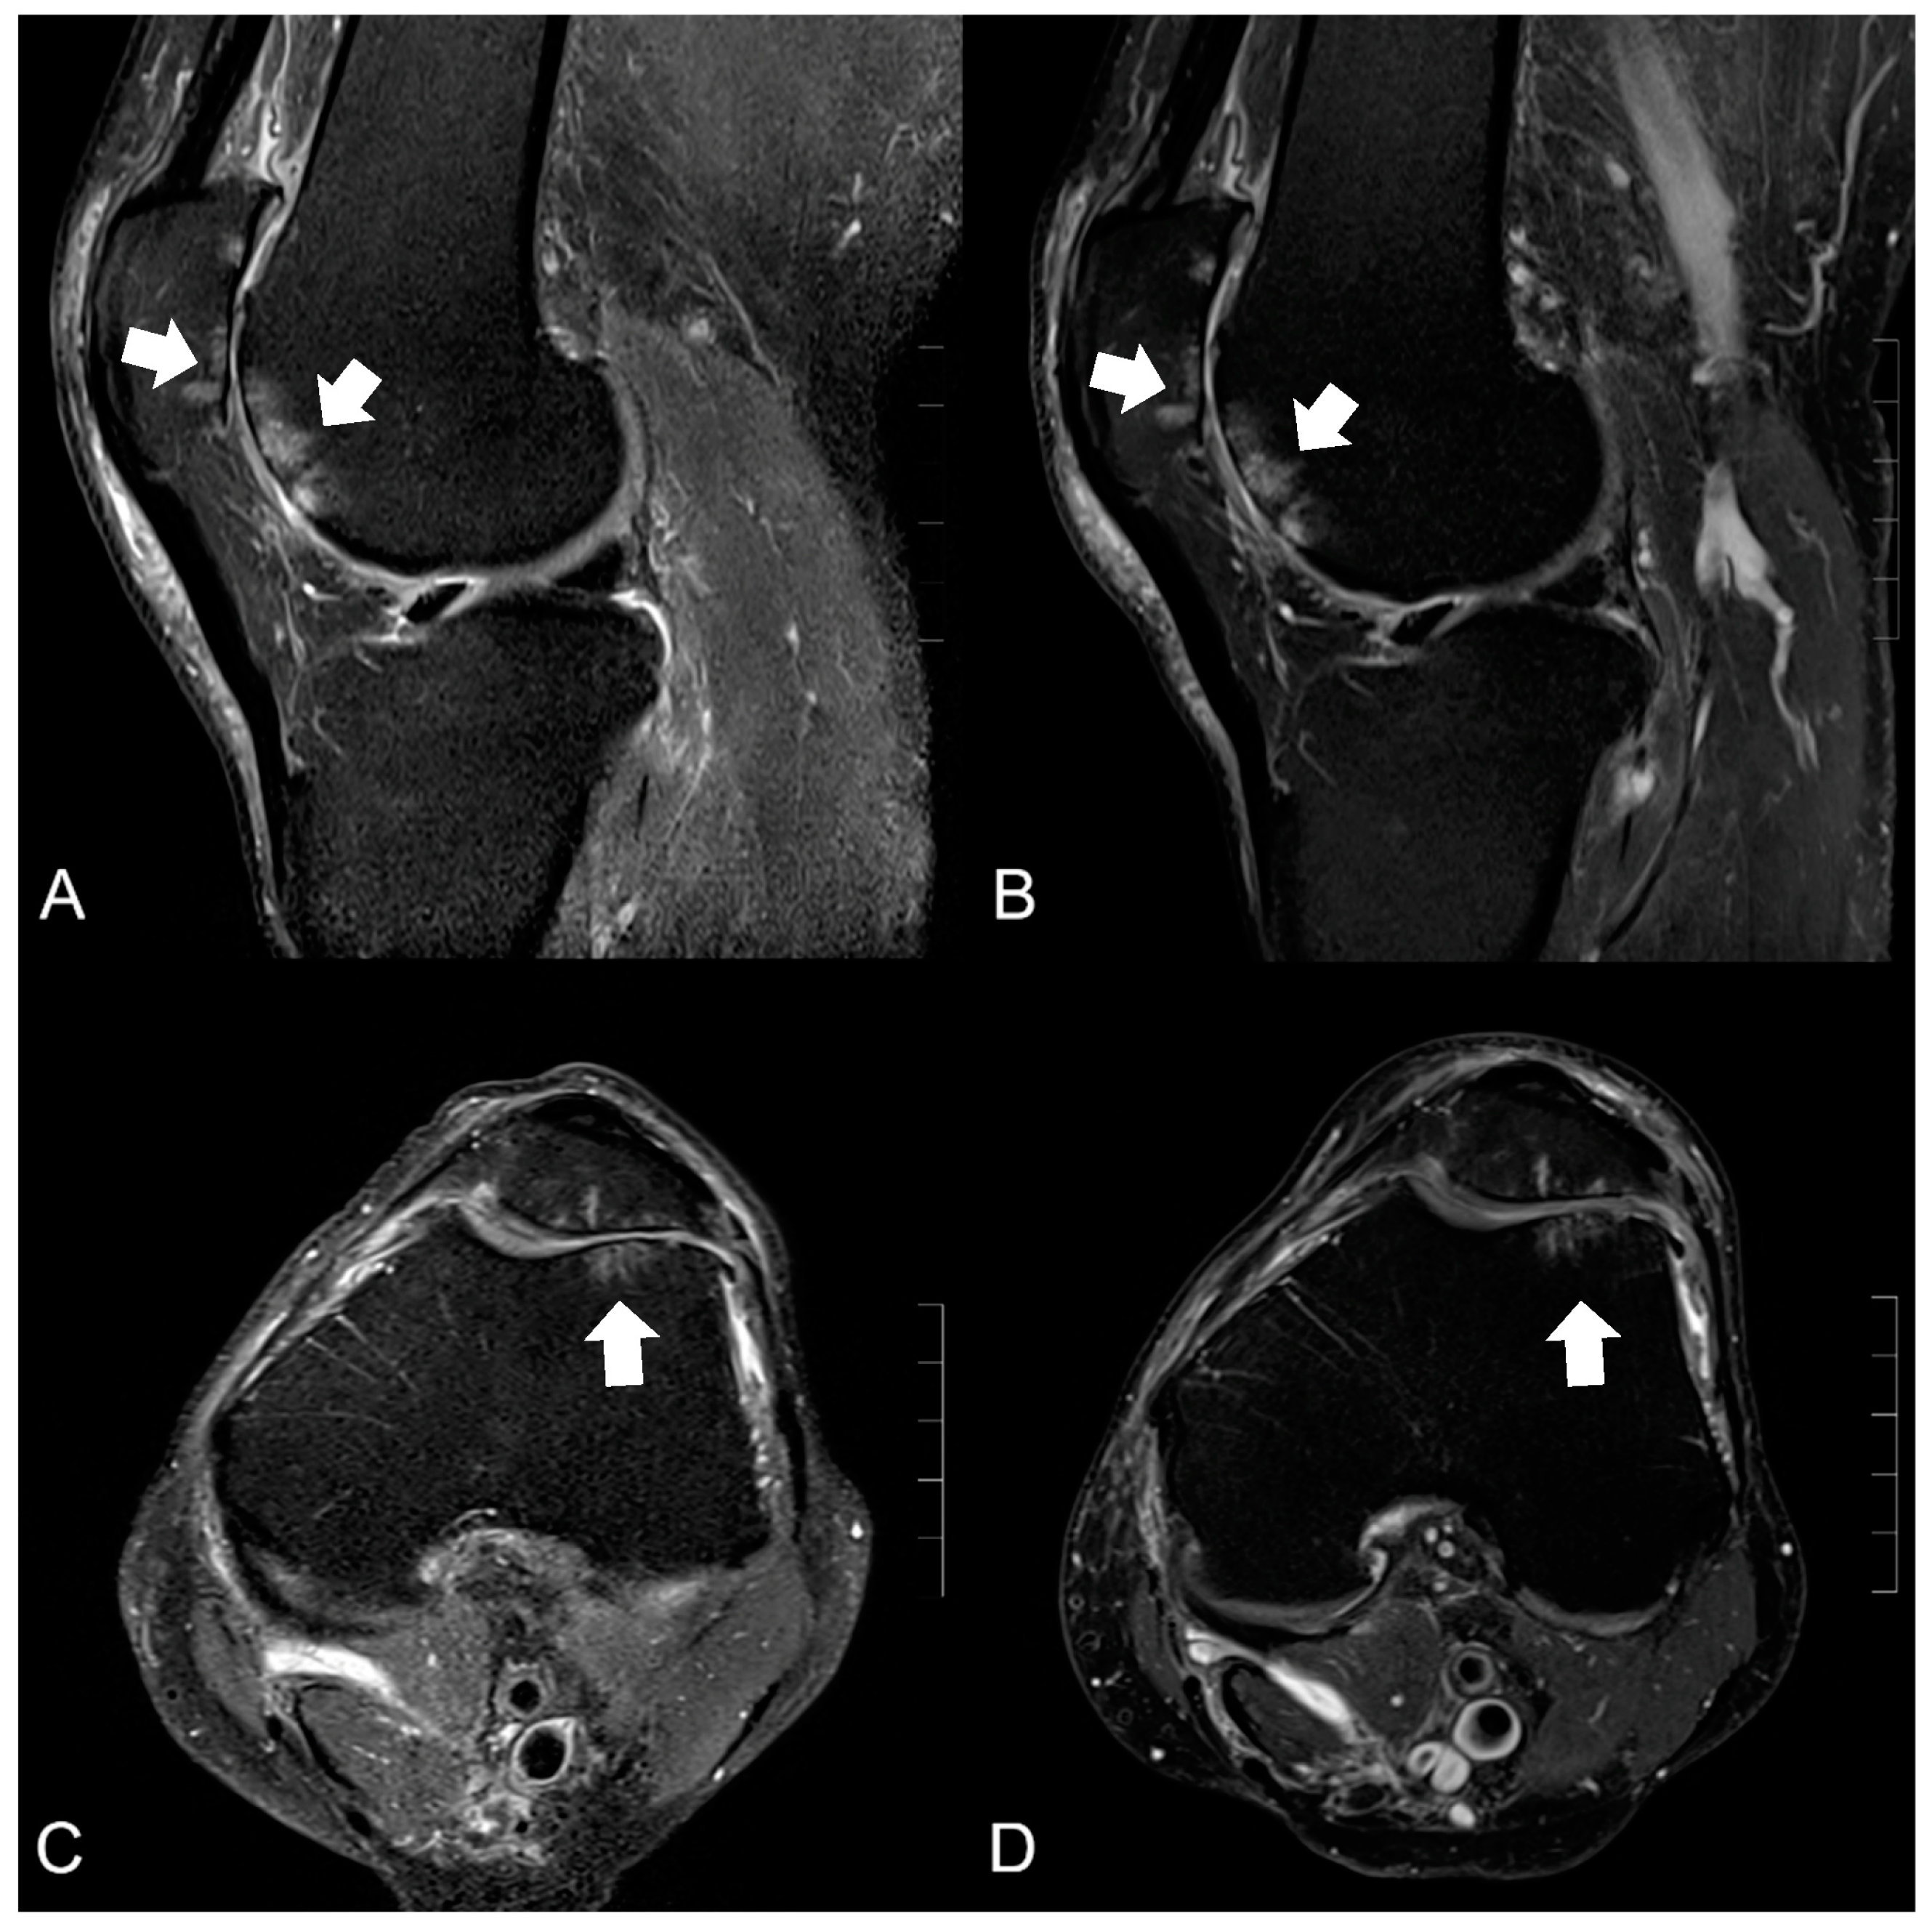

3.2. Visibility of Anatomical Structures and Detected Pathologies